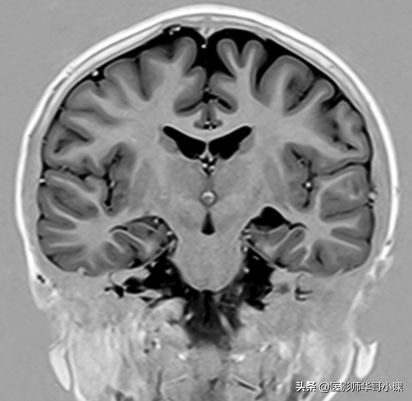

查阅相关资料,获得了颅脑灰白质、CSF以及皮下脂肪的T1弛豫时间。那么就可以根据这些参数作出其反转恢复纵向弛豫曲线了,如下图:

我们看到,脑白质的弛豫稍快于及灰质。脂肪最快,CSF最慢。下面我们需要将此观察对象的本征参数曲线与序列相结合,来更全面地来看下各参数的设置以及组织对比是如何被获取的。即 第四步 。

经过研究,TI=400ms的意义就是,当脑白质过零时,施加90度激励脉冲采集信号。这里400ms只是一个经验值,不是很精准的。但为什么是白质过零时采集呢?稍后讲。我们先来看看,这个白质过零时间到底是多少。

模图采集,只关心矢量的大小,不关心其方向(即是正矢量还是负矢量),那么对应到灰阶时就是,量的绝对值越大,越白;绝对值越小(即越接近于零矢量),越黑。我们对照模图M来看,在脑白质过零时采集,那么由于脂肪比脑白质弛豫快,那么其矢量已经恢复到正方向且有较大的值 ,在M图上表现为较高信号(亮);脑灰质由于比脑白质弛豫慢,那么采集时其仍在恢复,但其还没有达到零,仍有较少的负矢量,那么在M图上表现为稍高信号(灰);脑脊液由于拥有很长的T1值,那么其弛豫是非常慢的,采集时,其仍拥有很大的负矢量,那么在M图上就表现为高信号(亮);但由于采集时脑白质刚过零,那么其矢量为零,在M图像上就对应最黑,跟空气差不多(背景是黑色),即无信号。

实图采集,不仅关心矢量的大小,也关心其方向(即是正矢量还是负矢量),那么对应到灰阶时就是,最大正矢量对应最白;最大负矢量对应最黑,零矢量对应正中间的灰色,即背景为灰色(空气是没有信号的)。我们对照实图R来看,在脑白质过零时采集,那么由于脂肪比脑白质弛豫快,那么其矢量已经恢复到正方向且有较大的值,在R图上表现为较高信号对应到灰到白的灰阶,即亮白;脑灰质由于比脑白质弛豫慢,那么采集时其仍在恢复,但其还没有达到零,仍有较少的负矢量,那么在M图上表现为较低信号,对应着灰到黑的灰阶,即灰黑色;脑脊液由于拥有很长的T1值,那么其弛豫是非常慢的,采集时,其仍拥有很大的负矢量,那么在R图上就表现为更低的信号,趋于黑色;但由于采集时脑白质刚过零,那么其矢量为零,在R图像上就对应灰色,跟背景一个灰阶。

好了,实图与模图已经搞清楚了。那么我提个问题,我们常规的颅脑T1反转恢复序列一般都是采用的模图M,那么其TI反转时间是多少呢?能根据信号公式计算出最优时间吗?还有就是研究过了这个序列,就会立马想到STIR,FLAIR序列跟这个不是一个大家庭的吗?可谓不攻自破(“不研即会”)。接着,就会想到进阶序列,双反转、三反转等。